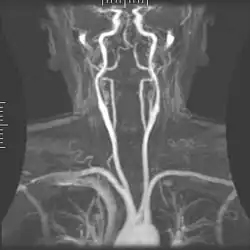

Magnetic resonance angiography (MRA) generates pictures of the arteries to evaluate them for stenosis (abnormal narrowing) or aneurysms (vessel wall dilatations, at risk of rupture). MRA is often used to evaluate the arteries of the neck and brain, the thoracic and abdominal aorta, the renal arteries, and the legs (called a "run-off"). A variety of techniques can be used to generate the pictures, such as administration of a paramagnetic contrast agent (gadolinium) or using a technique known as "flow-related enhancement" (e.g., 2D and 3D time-of-flight sequences), where most of the signal on an image is due to blood that recently moved into that plane (see also FLASH MRI).[53]

Techniques involving phase accumulation (known as phase contrast angiography) can also be used to generate flow velocity maps easily and accurately. Magnetic resonance venography (MRV) is a similar procedure that is used to image veins. In this method, the tissue is now excited inferiorly, while the signal is gathered in the plane immediately superior to the excitation plane—thus imaging the venous blood that recently moved from the excited plane.[54]